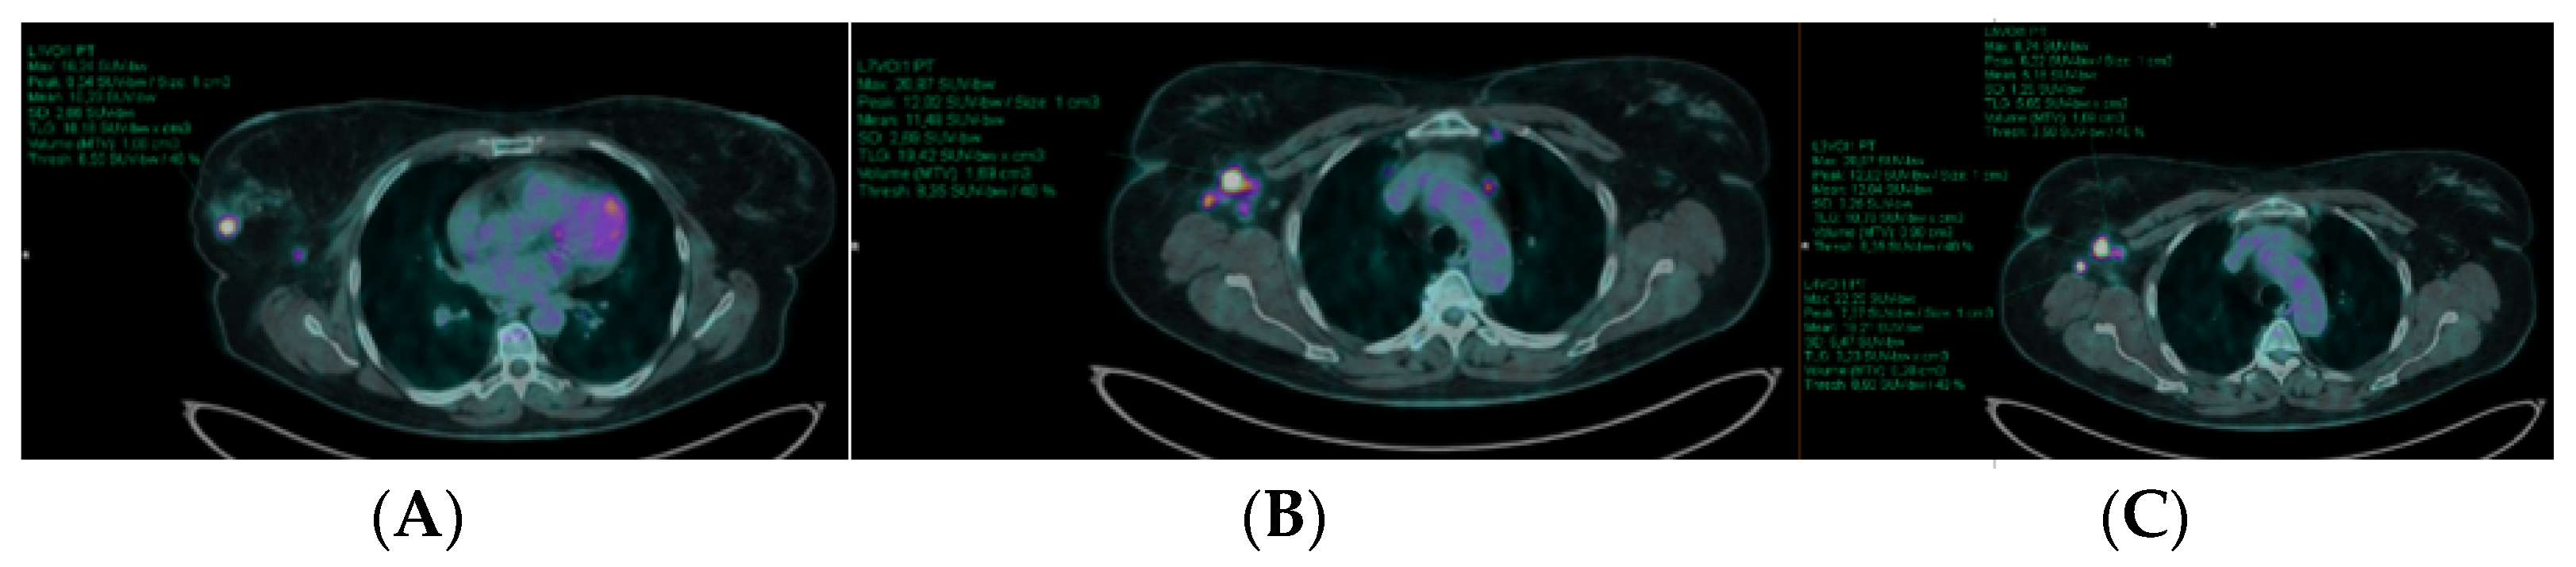

3.1. [18F]FDG PET/CT Results

3.2. [18F]FDG PET/CT Semiquantitative Data and Response to NAC